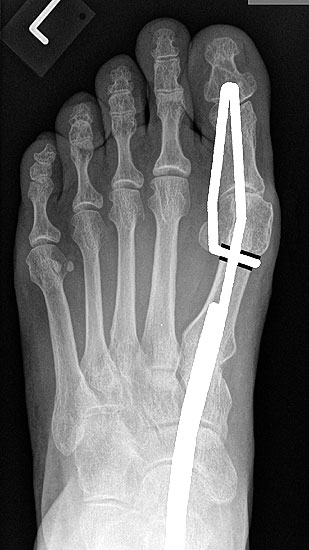

Die Röntgenaufnahmen (Abbildung 1) zeigen den Fuß einer 34 jährigen Patientin nach Exostosenabtragung. Der erhöhte intermetatarsale Winkel wurde durch eine alleinige Abtragung der Exostose nicht reduziert. Als weiterer Risikofaktor für ein Rezidiv liegt ein pathologischer Gelenkwinkel vor. Der intermetatarsale Winkel von 18 Grad kann durch eine basisnahe Osteotomie gut korrigiert werden. Da durch die gleichzeitige distale Korrektur des Gelenkflächenwinkels mithilfe einer Reverden-Green Osteotomie ein Längenverlust von ca. 2-4 mm einhergeht, bot sich als proximales Korrekturverfahren die basisnahe Open-wedge Osteotomie an, um bezüglich der Länge des Metatarsale I neutral zu bleiben (Abbildung 2). Die Kombination zweier verkürzender Verfahren (z.B. Lapidus und Reverden-Green) würden zu einem sehr kurzen ersten Strahl führen, mit dem Risiko einer Transfermetatarsalgie. Übersteigt die Verkürzung des Metatarsale I 2 mm, steigt das Risiko für die Entwicklung einer Transfermetatarsalgie deutlich an 8. Die durchgeführte Revision zeigt eine gute Stellung des 1. Strahls bei zentriert stehendem Gelenk.